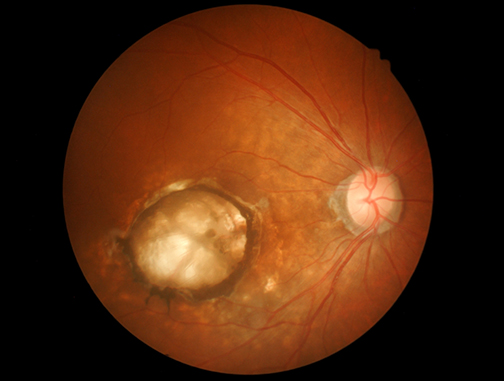

LSU Health New Orleans Researchers Discover a Key Failure in AMD that May Lead to Progression & Vision Loss

Research led by Nicolas Bazan, MD, PhD, Boyd Professor, Ernest C. and Yvette C. Villere Chair for the Study of Retinal Degeneration, and Director of the Neuroscience Center of Excellence at LSU Health New Orleans School of Medicine, suggests that age-related macular degeneration (AMD) decreases an essential fatty acid, preventing the formation of a class of protective molecules and reducing repair potential. The discovery may also open new therapeutic avenues for AMD. More

LSU Health New Orleans Develops New Human Cell Line to Study Blinding Eye Disorders

Under the direction of Boyd Professor Nicolas Bazan, MD, PhD, scientists at LSU Health New Orleans Neuroscience Center of Excellence have developed a new, experimental human cell line from retinal pigment epithelial cells. Called ABC, these cells so closely resemble and retain the properties of native retinal pigment epithelial (RPE) cells, the research team has shown that they are a reliable cell system to study retinal degenerative diseases. More

LSU Health Contributes to Research Suggesting Late-Onset Retinal Degeneration Mechanism & Potential Rx

A study led by the National Eye Institute (NEI) that included five researchers from the Bazan Lab at the LSU Health New Orleans Neuroscience Center of Excellence has discovered how late-onset retinal degeneration can develop and a surprising potential therapeutic -- metformin. The results are published online in Communications Biology, a Nature journal. More